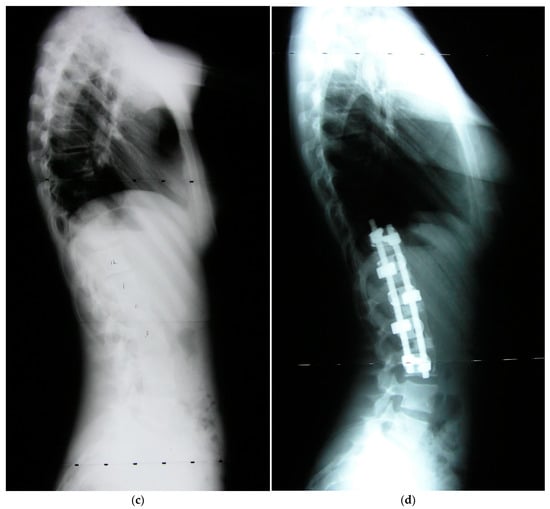

Figure 1.

Preoperative coronal and sagittal radiographs (a,c) and postoperative radiographs (b,d). (a) AIS Type 5 preoperative coronal (upright indicated by arrow) radiograph with 60 degrees scoliosis. (b) Postoperative radiograph at one year after traditional convex technique.